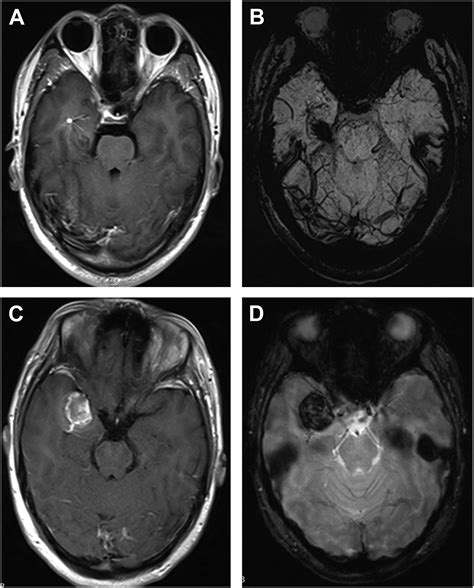

While DVAs are generally considered benign, they can sometimes be associated with other vascular malformations, such as cavernous malformations or arteriovenous malformations (AVMs). These associations can complicate the clinical picture and may require more aggressive management strategies.

Diagnosing a DVA typically involves imaging studies, such as magnetic resonance imaging (MRI) or computed tomography (CT) scans. These imaging techniques can reveal the characteristic appearance of DVAs, which include:

• Abnormal venous channels

• Dilated venous structures

• Caput medusae appearance, where the venous channels radiate outward like the head of Medusa

In some cases, additional imaging studies, such as angiography, may be performed to better visualize the venous drainage patterns and rule out other vascular malformations.